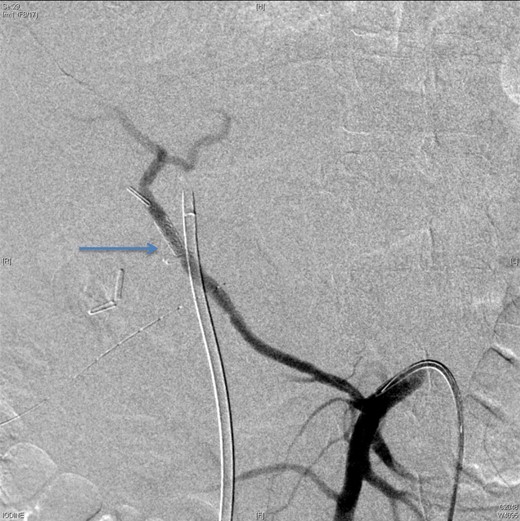

An angiographic scan showed stent in the replaced right hepatic artery.